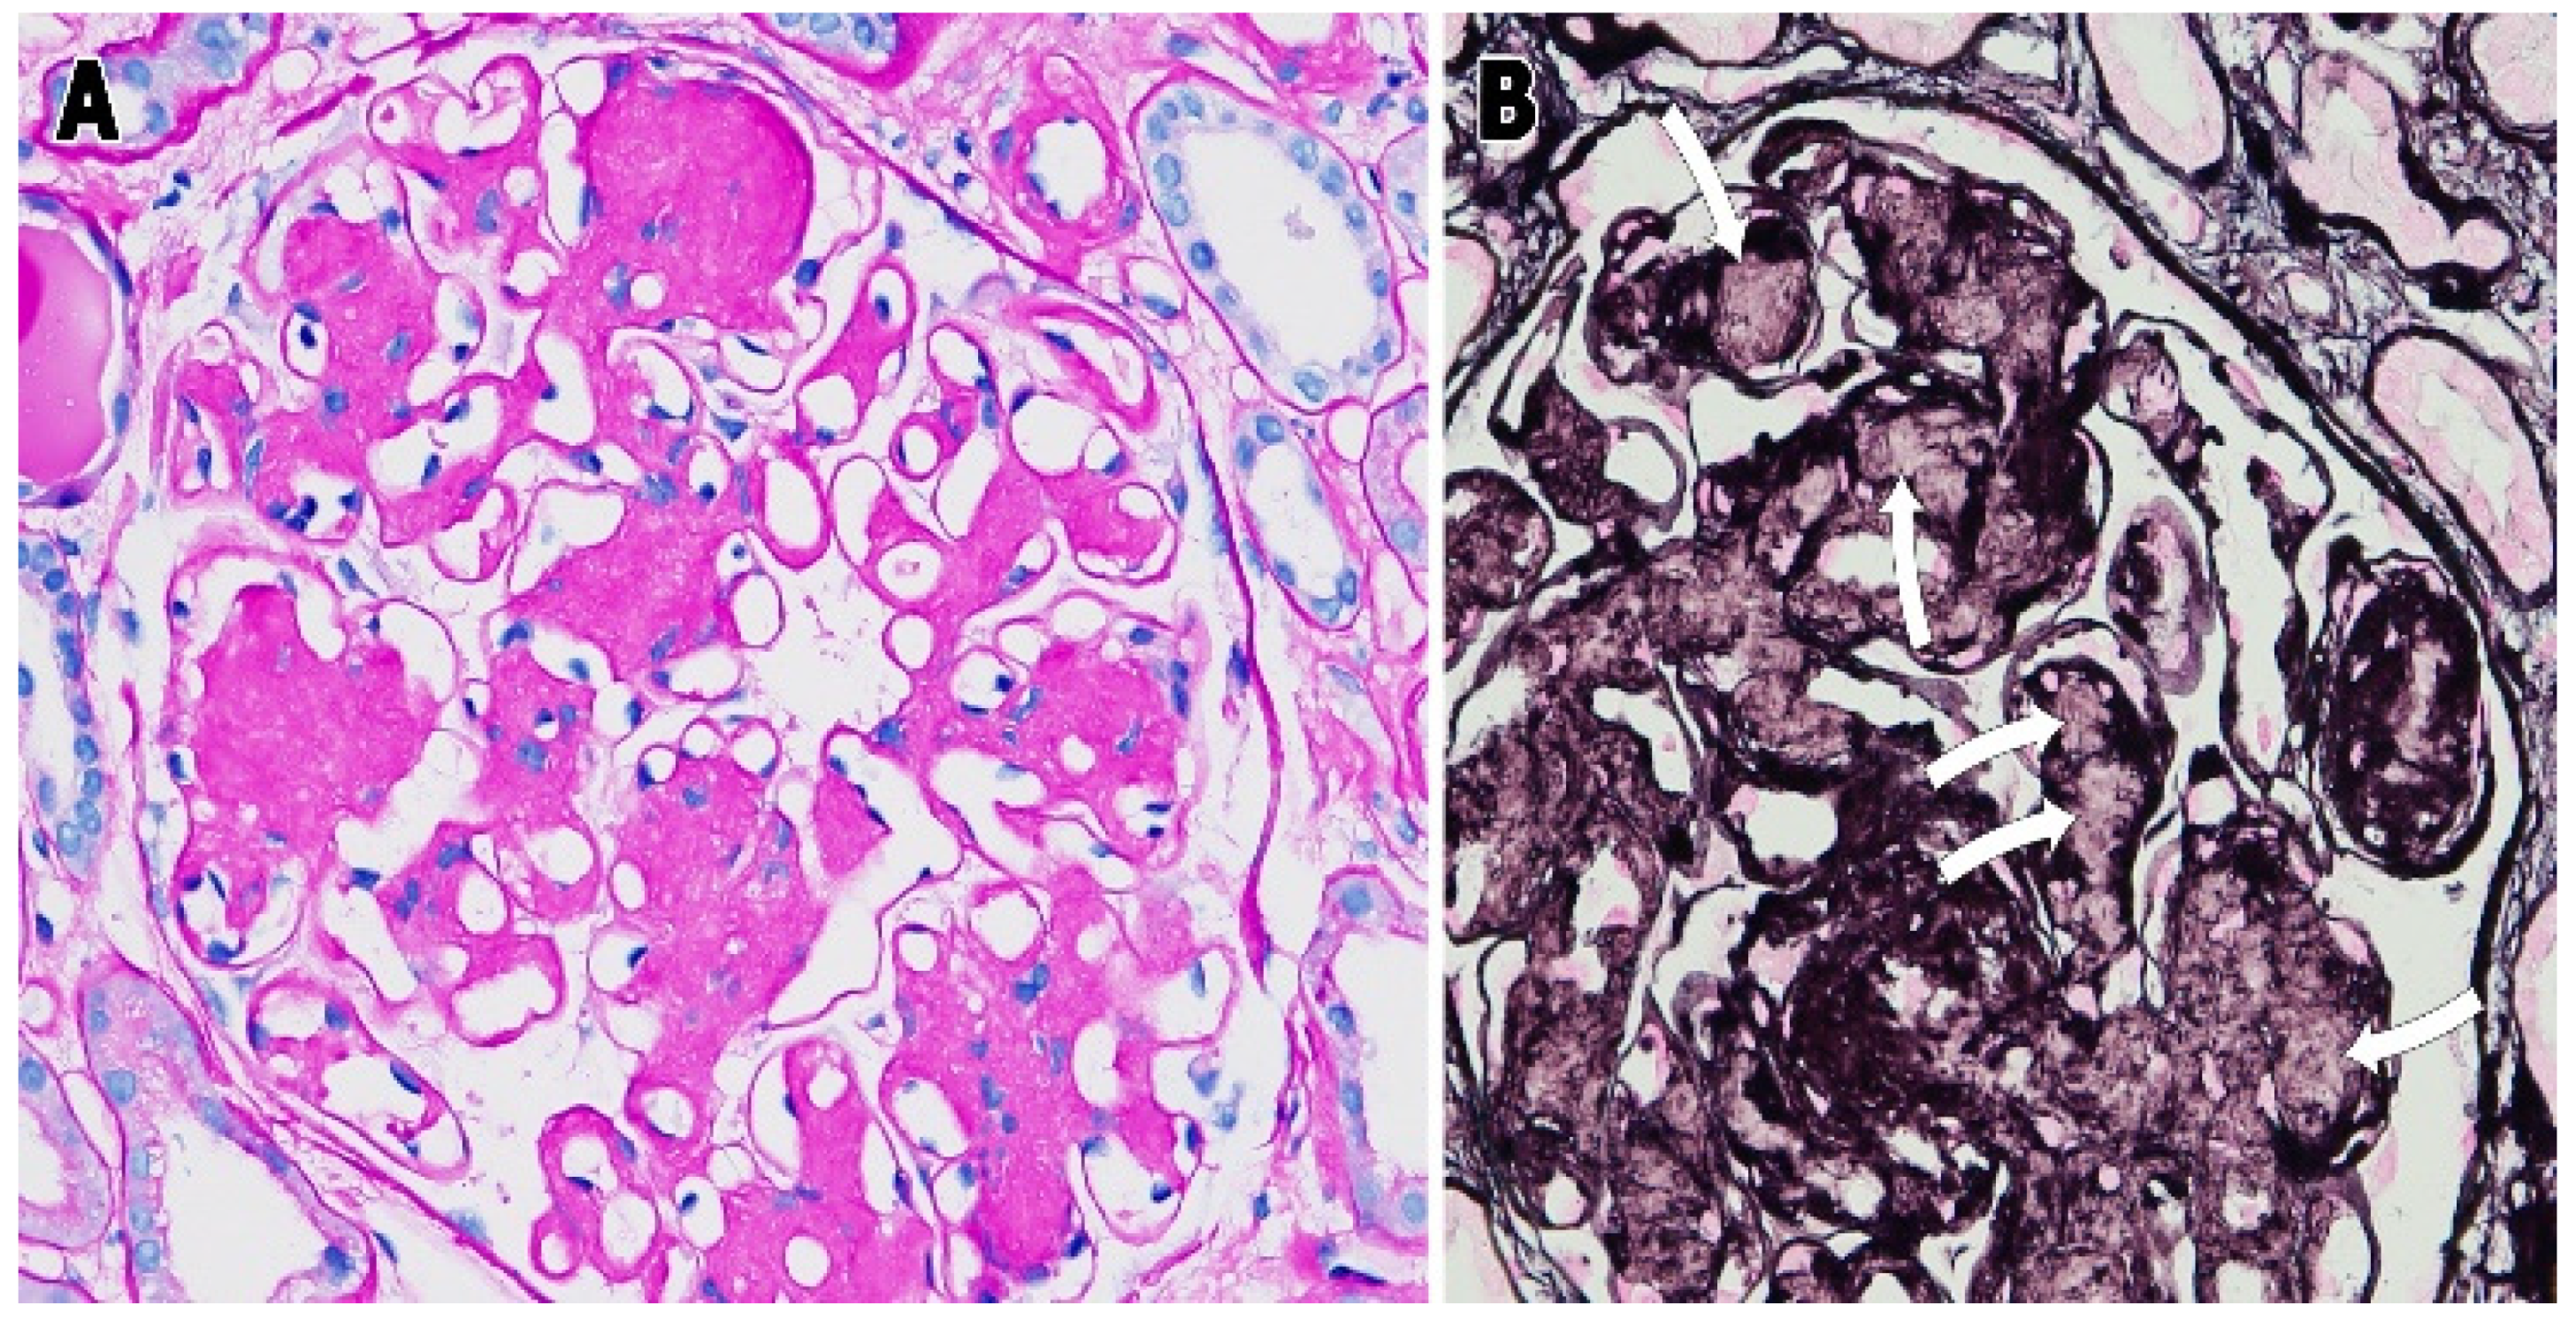

Fibril-Forming Organelles in Mesangial Cells in Renal Biopsies from Patients with Light-Chain-Associated Amyloidosis

3. Results